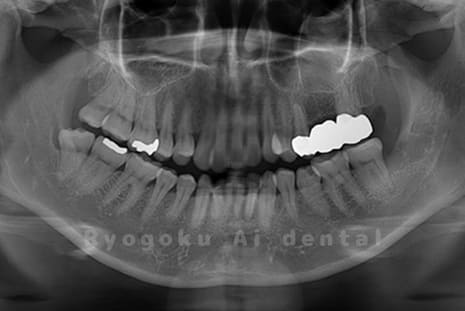

真っ直ぐ生えている親知らず

親知らずが真っ直ぐ生えているタイプです。

このタイプは真っ直ぐ生えていて咬み合わせに問題がなければ、抜歯しないケースもあります。ただし、虫歯になっていたり、痛みがあったり、咬み合わせが悪かったりすると抜歯をおすすめします。